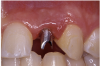

Periapical radiographs were taken to help determine the mesial-distal inclinations of the adjacent tooth roots (Figure 1). The radiographs revealed a serious issue, convergent roots for the right canine and right central, which eliminated that area as a potential implant-receptor site. The space between the left central and canine teeth was minimal, although the roots were relatively parallel. Clinical examination (manual palpation of the root eminences superiorly to the vestibule on the right side) confirmed the root convergence (Figure 2A). The flat, wide zone of the keratinized tissue and lack of interdental papilla was evident for the missing right lateral incisor. There was a marked difference in clinical appearance for the left lateral, which could impact the eventual plan of treatment (Figure 2B). Other significant clinical findings included bilateral facial bone concavities, which existed as a result of the congenitally missing tooth roots. As a diagnostic cue to the underlying bone topography, it is important to follow the demarcation between attached and unattached gingival tissue, and note the crestal width of the available keratinized tissue (Figure 2C).

Figure 2a  Pretreatment buccal views showed (A) root convergence, (B) a difference in clinical appearance of the left lateral, and (C) significant crestal width of keratinized tissue.

Figure 2a